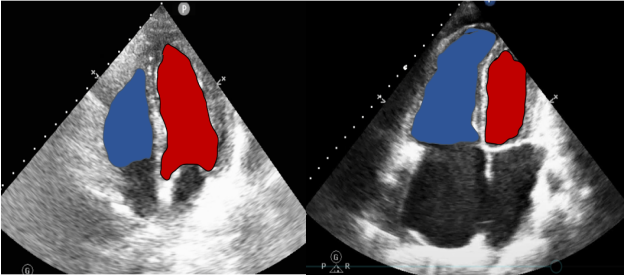

对肺循环而言,我们评价的思维和体循环一致。作为一个低容量低阻力系统,肺循环需要我们关注的点和体循环不同。在非超声评价手段中,我们常规选择PAWP或GEDI作为体循环前负荷的指标,而CVP作为或舒张期右室容积作为肺循环前负荷的指标;左室和右室的射血分数常规作为体循环和肺循环收缩力的评价指标;体循环阻力指数和肺循环阻力指数作为体循环和肺循环后负荷的评价指标。以下将详细阐述重症超声如何评价肺循环系统。首先仍为前负荷的评价。右心室作为唯一一个可以急性扩张的心脏腔室,临床上较难直接测量相关的容积和压力参数作为评价肺循环的前负荷直接指标,更多通过间接征象来评价。选择舒张末右心室的大小测量可作为一个指标。另外,更推荐在舒张末期,心尖四腔心切面,测量右心室面积和左心室面积的比值,若该比值在0.6以内,则表明右心无明显扩张;若该比值在0.7~0.9之间,为中度扩张;若大于1,则代表右心的重度扩张。相关测量示意图如图10所示。舒张末LV与RV面积对比测量示意图如图11所示。

图11 舒张末LV与RV面积对比测量示意图(左边比值正常,右边比值异常)